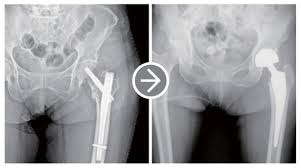

- 반치환술(Hemiarthroplasty): 대퇴골 두부 골절 등 특정 상황에 고관절 반만 인공으로 바꿔주는 방식입니다.